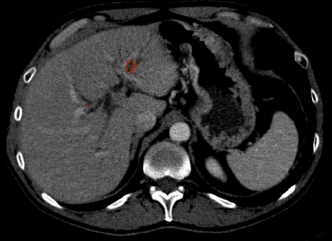

We preprocess the liver CT scans using a histogram based thresholding method. We select the rightmost peak of the intensity histogram distribution of a CT scan for normalization and use the histogram equalization algorithm to generate the enhanced images as shown in Fig. 5. The implementation of the preprocessing and the liver lesion segmentation network is available online 111https://github.com/raun1/LITS_Hybrid_Comp_Net.